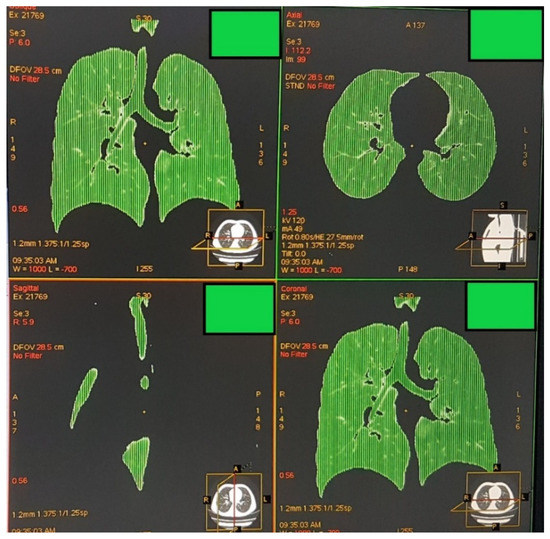

2.2. Image Acquisition, Analysis, and Definition of Attenuation Thresholds